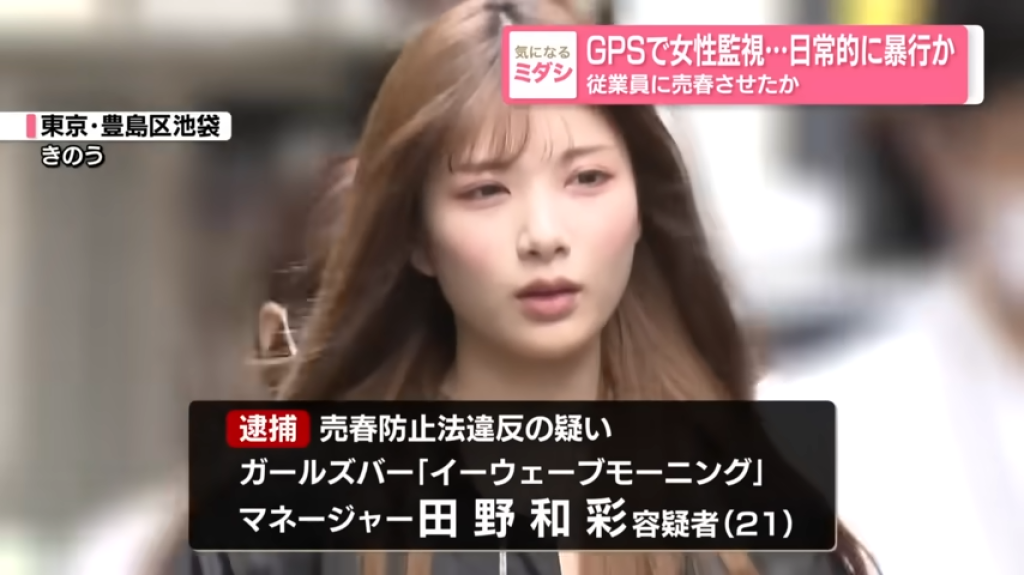

【警政時報 張家燁/新竹報導】一位75歲女性平時不菸不酒,今年於健康檢查安排LDCT肺癌篩檢,意外發現左下肺葉近3公分惡性腫瘤,求診中國醫藥大學新竹附設醫院胸腔外科謝義山醫師,經醫病溝通後,執行達文西微創手術,歷經4小時完成切除,病患術後三天順利出院,恢復情況良好。

謝義山醫師指出,患者十多年前曾罹患肺結核,導致肺部縱膈淋巴結硬化並與血管沾黏,手術中稍有不慎恐大出血,透過達文西機械手臂輔助,順利完成血管分離結紮,最終僅200cc出血,展現精準醫療優勢,術後建議病患逐步恢復日常,兩週可輕便活動,2至3個月後再進行重度運動。

謝醫師提醒,曾感染肺結核患者因肺部殘留病灶,罹患肺癌風險較一般人高出40至200倍,台灣女性肺癌患者中,80%至90%為不菸不酒族群,顯示基因遺傳及肺部結節也是重要風險因子,而有結核病史或家族史的女性,務必每年接受低劑量胸部電腦斷層篩檢,早期發現才能提高治癒率,肺癌初期常無明顯症狀,但若出現慢性咳嗽、咳血、胸痛、聲音沙啞、不明體重下降或反覆肺炎,應及早就醫。